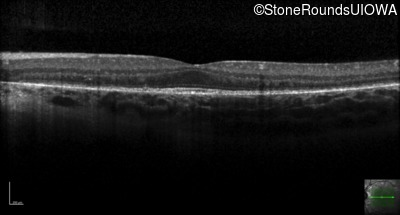

Age at visit: 11 years

OD OS

This 11 year old boy first had some fundus abnormalities noted during a routine eye exam at age 8. He remains asymptomatic. He has no difficulties seeing in dim light.